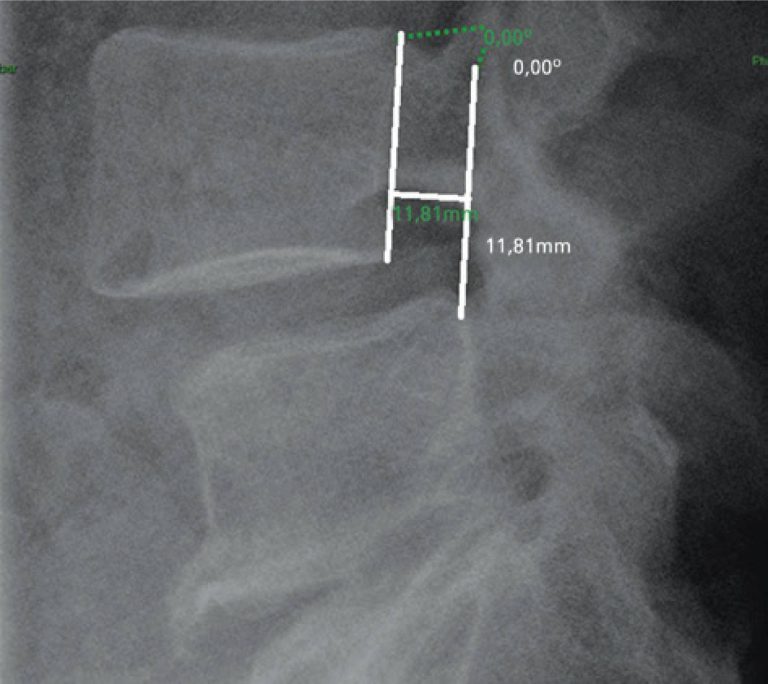

Reprodutibilidade interobservadores da avaliação radiográfica de instabilidade em coluna lombar

DOI: 10.1590/S1679-45082016AO3489

RESUMO Objetivo: Mensurar a reprodutibilidade interobservadores da avaliação radiográfica da instabilidade da coluna lombar. Métodos: Foram realizadas mensurações das radiografias dinâmicas de coluna lombar na incidência em perfil, avaliando-se a translação anterior e a angulação entre os corpos vertebrais. Os exames foram avaliados em workstations da própria instituição, por meio do sistema Vue RIS (PACS) da Carestream Health, versão 11.0.12.14 Inc. 2009©. Resultados: A proporção de concordância em detecção de casos de instabilidade radiográfica entre os observadores variou de 88,1 […]

Palavras-chave: Dor lombar; Espondilolistese; Instabilidade articular/radiografia; Região lombossacral/radiografia